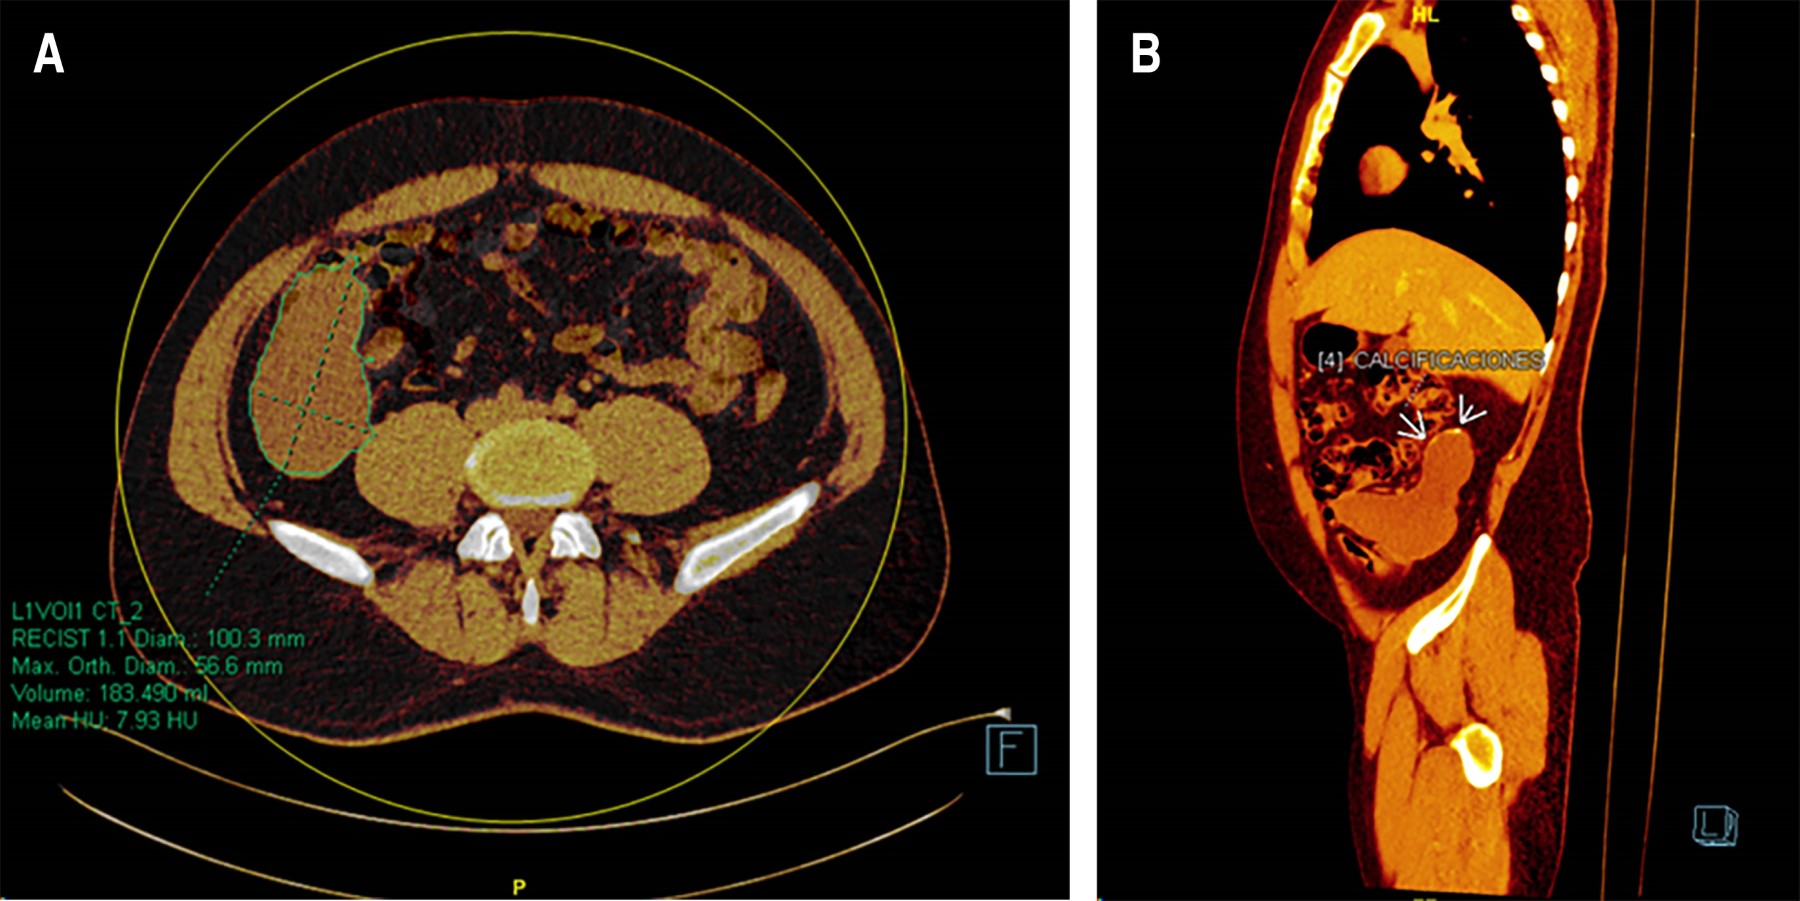

Paciente masculino de 35 años, sin antecedentes patológicos relevantes, consulta por dolor abdominal compatible con cólico vesicular de 48 horas de evolución. Se realiza ultrasonido abdominal, que confirma colelitiasis sin signos de colecistitis aguda. Como hallazgo incidental, se identifica una lesión quística bien definida en región retrocecal de 15 × 4.8 × 4 cm, sin signos de inflamación, con morfología compatible con mucocele apendicular. Se complementa el estudio con una TC abdominal, que revela apéndice retrocecal tubular, sobredistendido, con contenido hipodenso homogéneo y sin realce con contraste; diámetro apendicular de 10 × 5.6 cm, volumen de 183 ml y presencia de calcificaciones laminares en extremo distal del apéndice. No se evidencian lesiones nodulares, realce anormal o discontinuidad en la pared apendicular. La grasa periapendicular muestra densidad conservada, sin invasión a estructuras adyacentes ni adenopatías (Figura 1).

Figura 1